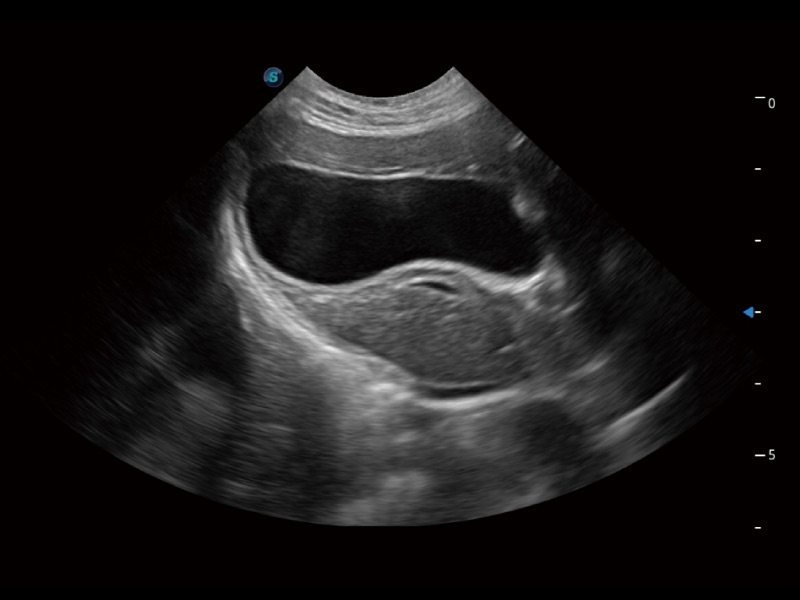

猫、中小型犬及小型异宠动物

一键自动识别膀胱壁及自动测量膀胱容积,不受膀胱形状和大小的限制,帮助医生快速精准获得测量的数据。